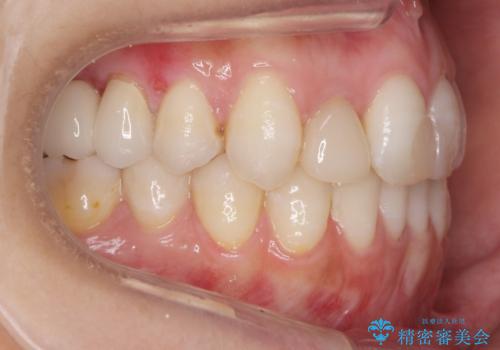

あきらめないで!!虫歯でボロボロでも大丈夫! 非抜歯矯正と虫歯、インプラント治療で見違える歯並びに。

途中矯正後に妊娠出産、育児等で2年以上中断を経た後虫歯治療の続きを行いました。最終的に治療完了まで行い状態は安定しています。